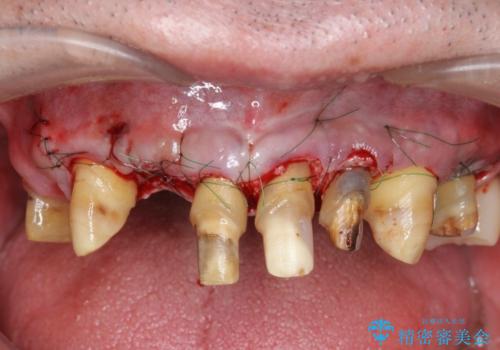

セラミック治療を行う前に歯周病の問題を解決すべく歯周外科を行い歯周ポケットを除去し整備したのちセラミックブリッジ・クラウンの製作を行います。

歯周外科を行ったことで非常に安定した歯周環境となり、引き締まった歯ぐきとなりました。